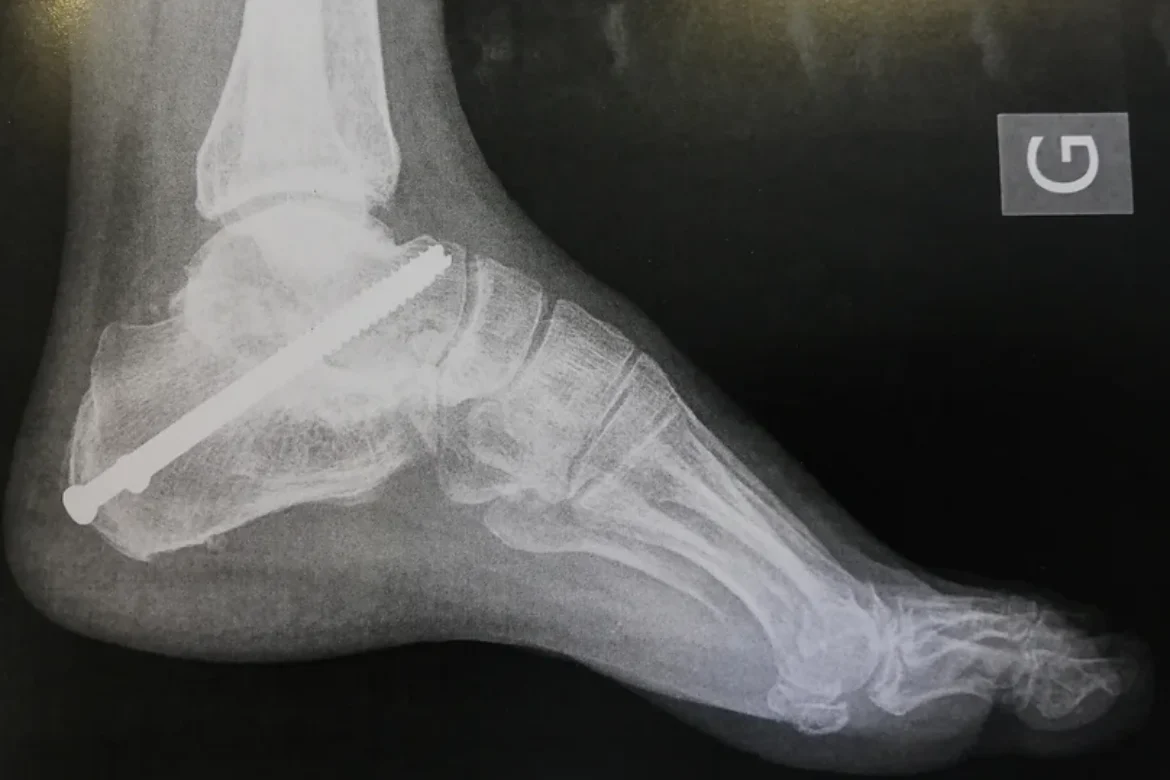

L’ARTHRODÈSE DE LA CHEVILLE

En savoir plus